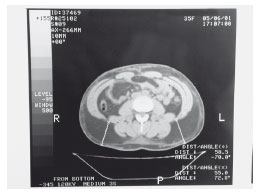

Grupo 1: 20 pacientes, com PC pré-operatório maior ou igual a 80 cm, submetidas à cirurgia de lipoaspiração ou lipoabdominoplastia, foram avaliadas com relação às suas medidas antropométricas. Grupo 2: 7 pacientes foram selecionadas segundo os mesmos critérios que o grupo 1 e foram submetidas à tomografia computadorizada no pré e pós-operatório, para determinar o que ocorre com a gordura visceral. Todas as pacientes foram orientadas a manter a mesma dieta que adotavam antes da cirurgia e a não fazer exercícios no período de 30 dias.

Observamos que todas as pacientes apresentaram diminuição significativa de suas medidas antropométricas, normalizando suas medidas ou migrando para um grupo de risco inferior ao seu. Porém, quando avaliamos a espessura intra-abdominal (EIA), observamos aumento ou manutenção nos números avaliados, demonstrando que a paciente não foi efetivamente emagrecida, pois o conteúdo intra-abdominal se manteve ou aumentou (aumento da gordura visceral).

Figura 1

Figura 2

Figura 3

Figura 4